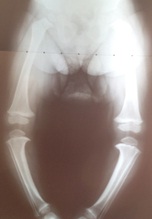

arcadas (Genu Varum).

Mary tem hoje 2 anos e 9 meses,

começou o uso das botas ortopédicas diurnas quando tinha 1 ano e 11 meses e

parou com 2 ano e 6 meses. Seu crescimento rápido e controle do peso foram